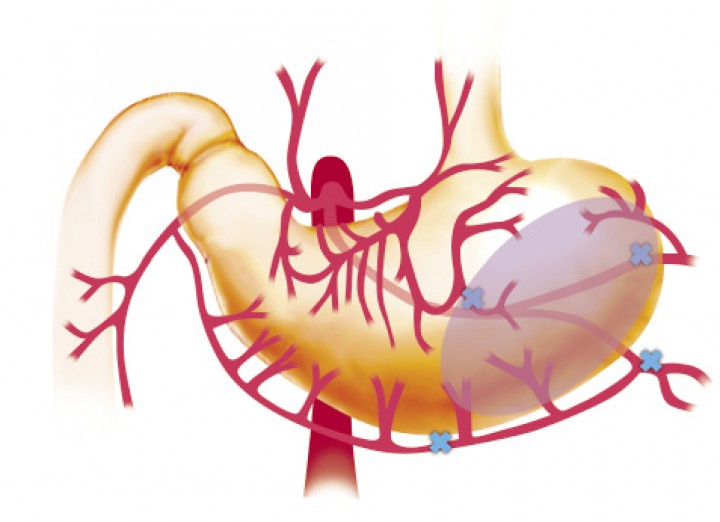

Aproximadamente en el 10% de los casos hay desvitalización de la pared gástrica y es necesaria la realización de una gastrectomía parcial. La zona que suele observarse más afectada es la curvatura mayor del estómago, debido a la frecuente ruptura de los vasos gástricos cortos procedentes de los vasos esplénicos y a la severa dilatación gástrica, que contribuye a la necrosis de esta zona (Figs. 10 y 11).[ Monnet E. Gastric dilatation-volvulus syndrome in dogs. Vet Clin Small Anim Pract 2003; 33: 987-1005. [PubMed] , Cornell K. Gastric dilatation and volvulus. En Tobias KM, Johnston SA (ed): Veterinary Surgery Small Animal. Vol. 2. St. Louis, Missouri, Elsevier Saunders, 2012; 1508-1510. ]

<p>Esquema representativo de la vascularización del estómago, estando marcados con (X) los vasos sanguíneos que con más frecuencia se dañan durante la DVG.</p>

Esquema representativo de la vascularización del estómago, estando marcados con (X) los vasos sanguíneos que con más frecuencia se dañan durante la DVG.